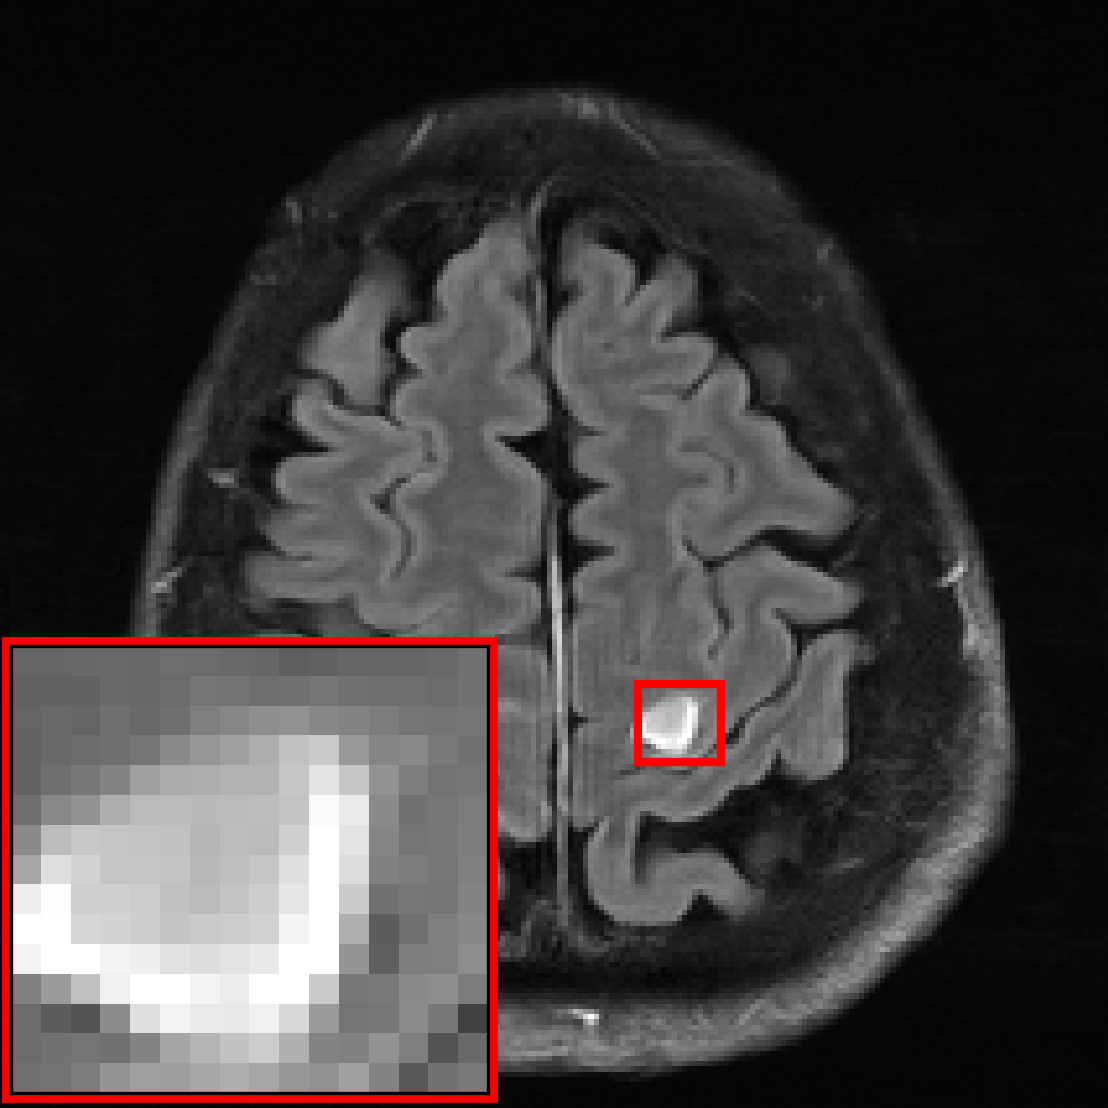

![[Uncaptioned image]](extracted/5298803/figs/pathology/lacunar_infarct_out_varnet.png)

![[Uncaptioned image]](extracted/5298803/figs/pathology/mass_out_varnet.png)

![[Uncaptioned image]](extracted/5298803/figs/pathology/lacunar_infarct_out_varnet_bl.png)

![[Uncaptioned image]](extracted/5298803/figs/pathology/mass_out_varnet_bl.png)

![[Uncaptioned image]](extracted/5298803/figs/pathology/lacunar_infarct_ref.png)

![[Uncaptioned image]](extracted/5298803/figs/pathology/mass_ref.png)

In this section, we investigate the distribution shift from healthy to non-healthy subjects by measuring how well models reconstruct images containing a pathology if no pathologies are contained in the training set. We find that models trained on fastMRI data without pathologies reconstruct fastMRI data with pathologies equally well as the same models trained on fastMRI data with pathologies.

We see that the models trained on show essentially the same performance (SSIM) as models trained on regardless of pathology size. The results indicate that models trained on images without pathologies can reconstruct pathologies as accurately as models trained on images with pathologies. This is further illustrated in Figure 6 (and Figure 16), where we show reconstructions given by the VarNet of images with a pathology: the model recovers the pathology well even though no pathologies are in the training set. Figure 14 in the appendix provides a more nuanced evaluation of the SSIM values for VarNet.